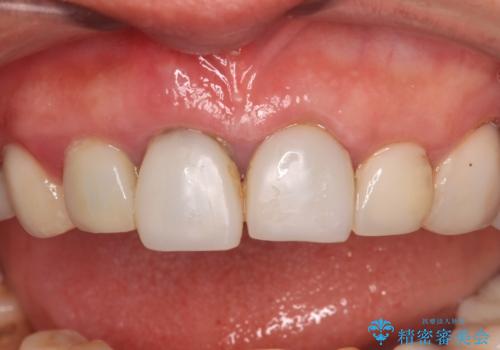

- 前歯が土台ごと外れてしまうとのことで来院された患者様です。

問題の歯は、歯根まで破折している状態で、抜歯が必要と判断されました。

周辺の歯は20年以上前に装着したクラウンで、色合いや形態が気になっているとのことで、オールセラミックブリッジにて補綴治療を行うこととしました。